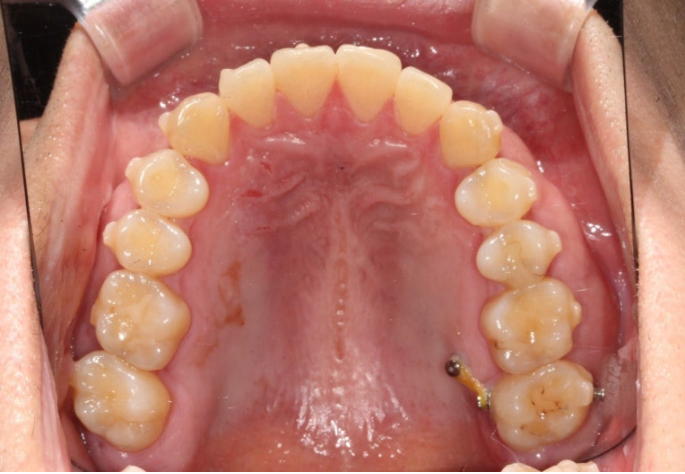

24.11

앞에서 보면 윗니가 아랫니를 많이 덮어서 앞니가 깊게 물리는 과개교합, 중심선 불일치,벌어진 앞니 등이 보입니다.

파란 화살표와 같이 물리는 상태를 가위교합이라고 합니다.

맨 뒤 큰 어금니에 흔하게 보이는 부정교합입니다.

위 어금니는 배열에서 바깥으로 나가있고

아래 어금니는 안으로 쓰러져 있습니다.

경미한 총생과 중심선 불일치, 가위교합, 벌어짐, 과개교합 문제가 있는 상황입니다.